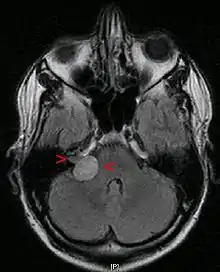

A vestibular schwannoma (VS) is a benign primary intracranial tumor[3] of the myelin-forming cells of the vestibulocochlear nerve (8th cranial nerve). A type of schwannoma, this tumor arises from the Schwann cells responsible for the myelin sheath that helps keep peripheral nerves insulated.[4] Although it is also called an acoustic neuroma, this is a misnomer for two reasons. First, the tumor usually arises from the vestibular division of the vestibulocochlear nerve, rather than the cochlear division.[5] Second, it is derived from the Schwann cells of the associated nerve, rather than the actual neurons (neuromas).[6]

| Bilateral schwannomas in a patient with neurofibromatosis 2 | |

Although there is an inheritable condition, Neurofibromatosis Type 2 (NF2), which can lead to acoustic neuroma formation in some people,[3] 95% of acoustic neuromas occur spontaneously without any evidence of family history.[9] NF2 occurs with a frequency of 1 in 30,000 to 1 in 50,000 births. The hallmark of this disorder is bilateral acoustic neuromas (an acoustic neuroma on both sides) usually developing in late childhood or early adulthood, frequently associated with other brain and spinal cord tumors.